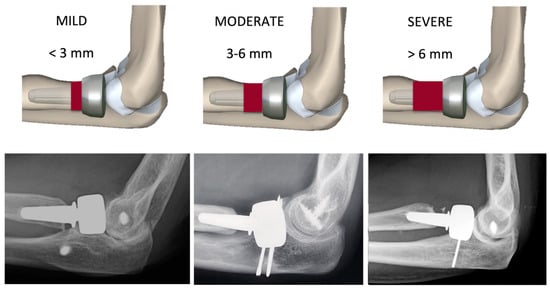

At the last follow-up, the mPRNR was classified into 3 different grades: mild (<3 mm resorption), moderate (3–6 mm resorption), and severe (>6 mm resorption) (Figure 2). The 3 mm cut-off was chosen on the basis of the mean total length of the radial neck (normally from 8 to 9 mm); in particular, we considered the anatomical distance between the lower margin of the radial head articular surface on its ulnar side, which corresponds to the lesser sigmoid notch, and the proximal margin of the bicipital tuberosity of the radius [6,7]. The number of neck quadrants involved for each mPRNR grade was recorded.

Figure 2.

Classification of proximal radial neck resorption (PRNR). The degree of PRNR was classified into three grades: mild (PRNR < 3 mm), moderate (PRNR 3–6 mm), and severe (PRNR > 6 mm).